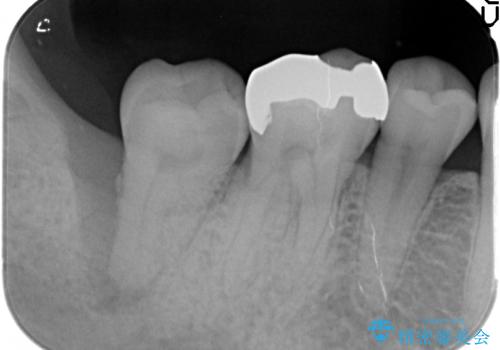

- 右下奥歯がグラグラし、噛めないことの改善を希望され来院されました。

X線写真より根尖付近までの骨吸収を認めます。

抜歯を余儀なくされる状況ですが、将来的にインプラントによる咬合機能回復を希望されたので抜歯と同時に骨補填剤を填入し骨の造成をしたのちのインプラント治療を計画します。